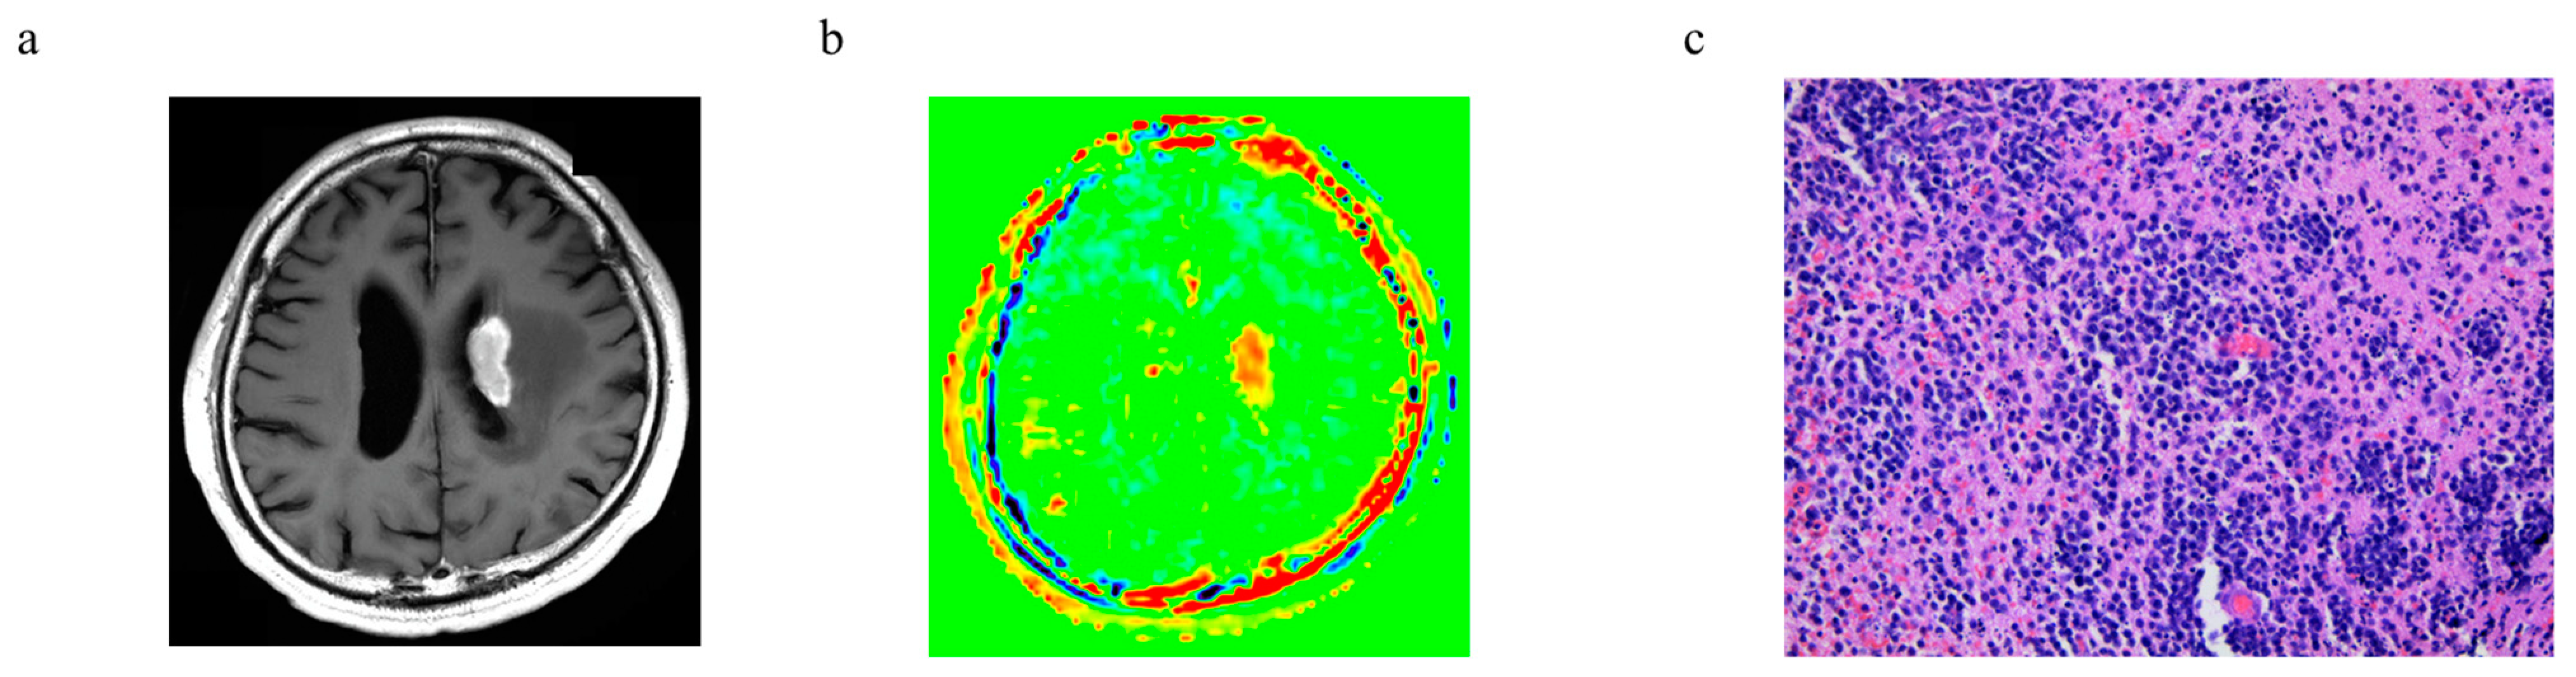

3.6. Representative Cases